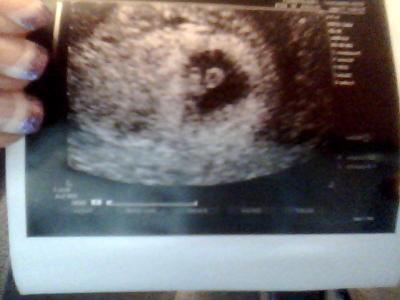

Hallo Mädels bin so über glücklich alles super entwickelt und das Herz hat geschlagen juhu . Heute 6+6

Bild zu War heut beim Frauenarzt + Bild - Forum für Oktober - Mamis